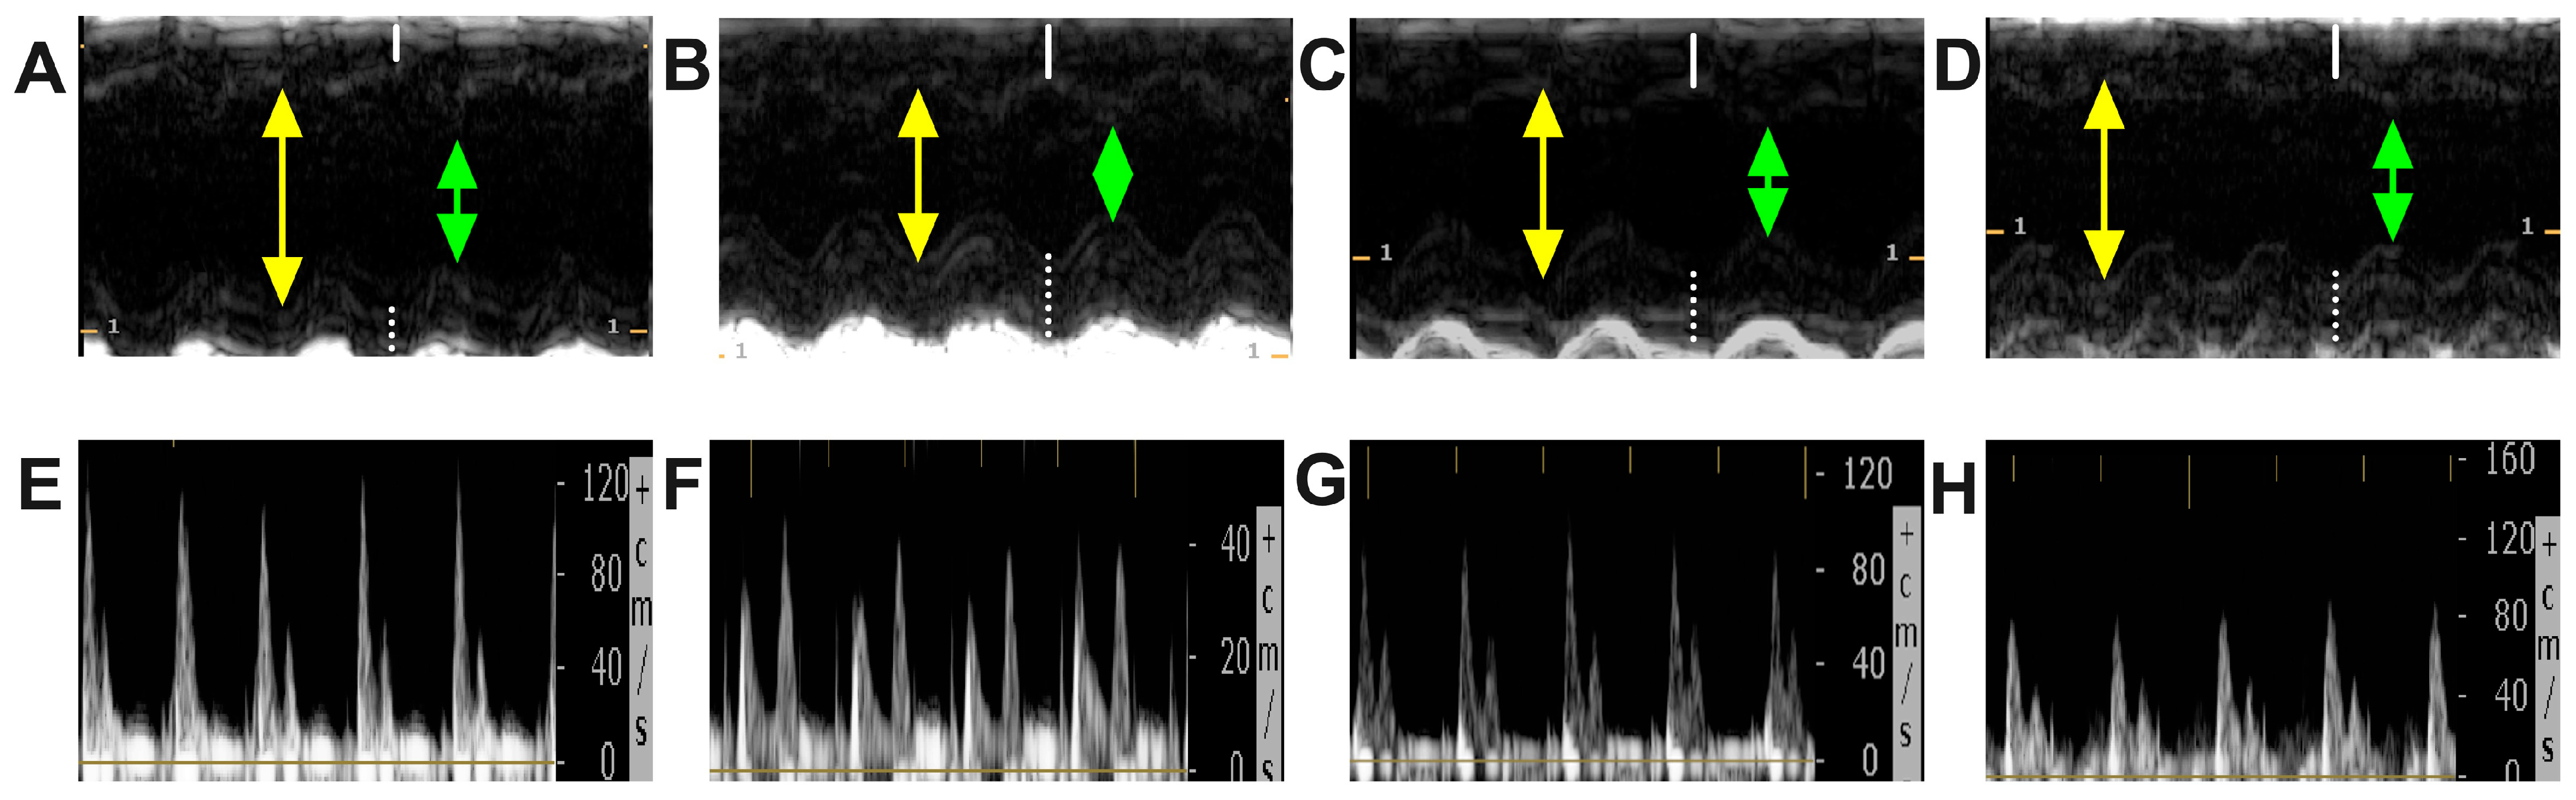

2.4. Effect of Chitosan and Dapagliflozin on LV Dimensions and Functions

4.3. Echocardiography